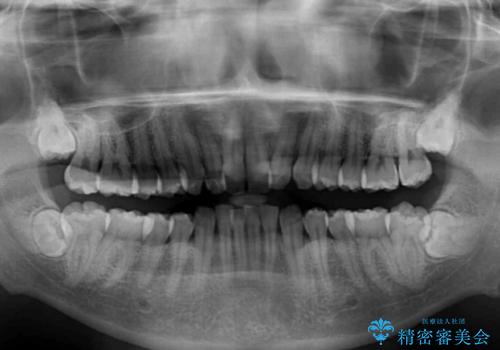

口元の突出感はないものの、上顎前歯のデコボコが著しかったため、上顎左右第一小臼歯2本を抜歯することとしました。

咬合力が非常に強く、抜歯したスペースがなかなか閉じないであろうことは予想できましたが、思っていた以上に期間がかかりました。

前歯のすり減りも著しかったため、仕上げの位置の調整にも期間を要しました。